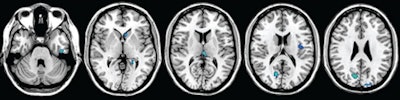

| MR images show regions of decreased gray-matter volume at one-year follow-up in patients with clinically isolated syndrome (CIS). Significant clusters (light blue) of CIS are overlaid on the brain axial sections. Scattered volume reductions are found in several cerebral gray-matter regions, including the thalami, cuneus, paracentral lobule, insula, temporal cortex, caudate head, and supplementary motor areas. Images courtesy of Radiology. |

The study's longitudinal volumetric analysis showed a significant reduction in global gray-matter volume, while the VBM analysis showed the development of regional gray-matter atrophy in several cortical and subcortical regions in both hemispheres. There was no significant longitudinal change in global or regional white-matter fractional anisotropy.

"It is beyond dispute that the correlation between the one-year follow-up gray-matter volumes and the baseline fractional anisotropy of white matter in our patients is strong," Raz and colleagues wrote. "Gray-matter atrophy increased significantly during the first year after the clinical onset of multiple sclerosis, whereas white-matter damage, which is present from the beginning, did not change significantly in the same time interval."